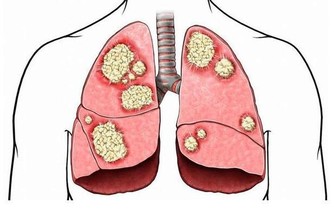

咳嗽是呼吸系統中最常見的症狀之一,是人體的一種保護性措施,對機體是有益的。當呼吸道黏膜受到異物、炎症、分泌物或過敏性因素等刺激時,即反射性地引起咳嗽,有助於消除自外界侵入呼吸道的異物或分泌物、消除呼吸道刺激因子。

這樣咳嗽是壞事

所以,出現咳嗽症狀時,做好保暖的同時,還需補充大量的水分,同時避免胡椒、洋蔥等辛辣食物刺激呼吸道。如頻繁咳嗽還伴有發燒、胸痛、體重減輕等症狀時,就立即就醫。